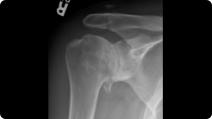

Radiographic image of a clavicle fracture Radiographic image of a clavicle ORIF (plate and screws)

Clavicle Fracture

Clavicle ORIF (Plate and Screws)